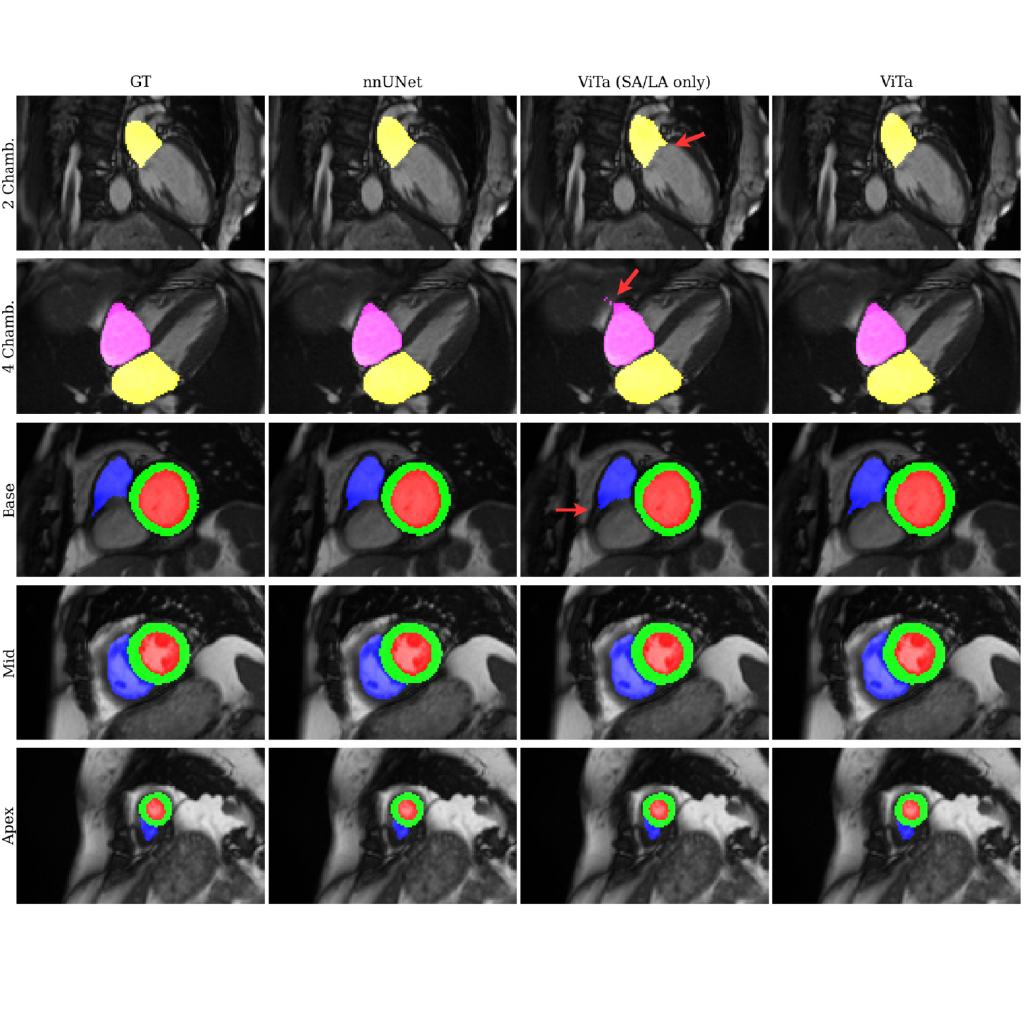

ViTa: A Multi-Modal Foundation Model for Cardiac MRI

Suprosanna Shit of the DQBM contributed to a large-scale study presenting ViTa, a foundation model integrating cardiac MRI with patient data for comprehensive heart assessment.